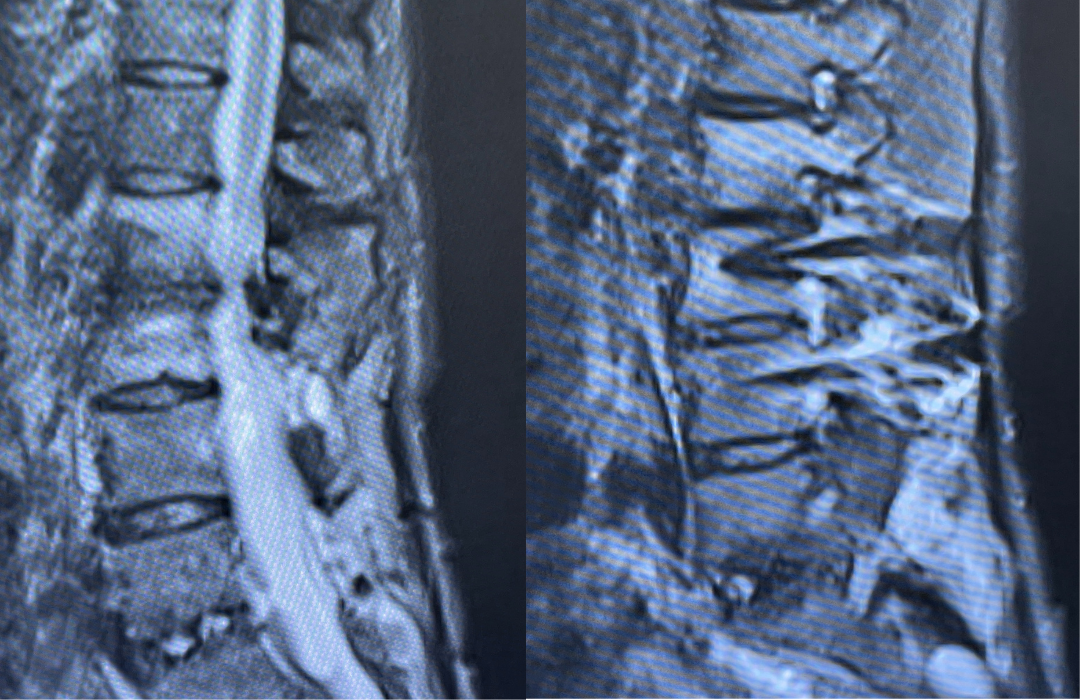

Noninvasive vascular imaging was sufficiently suggestive to warrant conventional digital subtraction angiography, performed by Dr. Brisman and confirming Moya-Moya syndrome (Figures 1). CT Perfusion (Figure 2) showed a decreased transit time of blood to the right hemisphere and the patient was recommended to undergo cerebral revascularization to avert stroke.